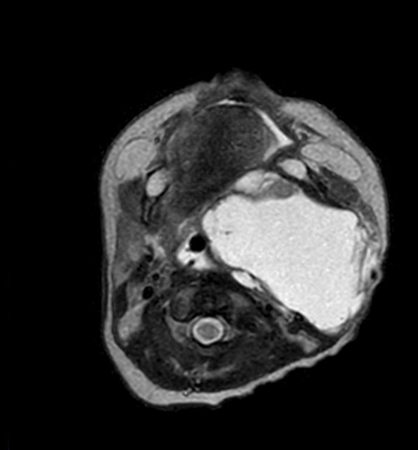

Axial mDIXON XD - T2w TSE (Water only)

Axial mDIXON XD - T2w TSE (In Phase)